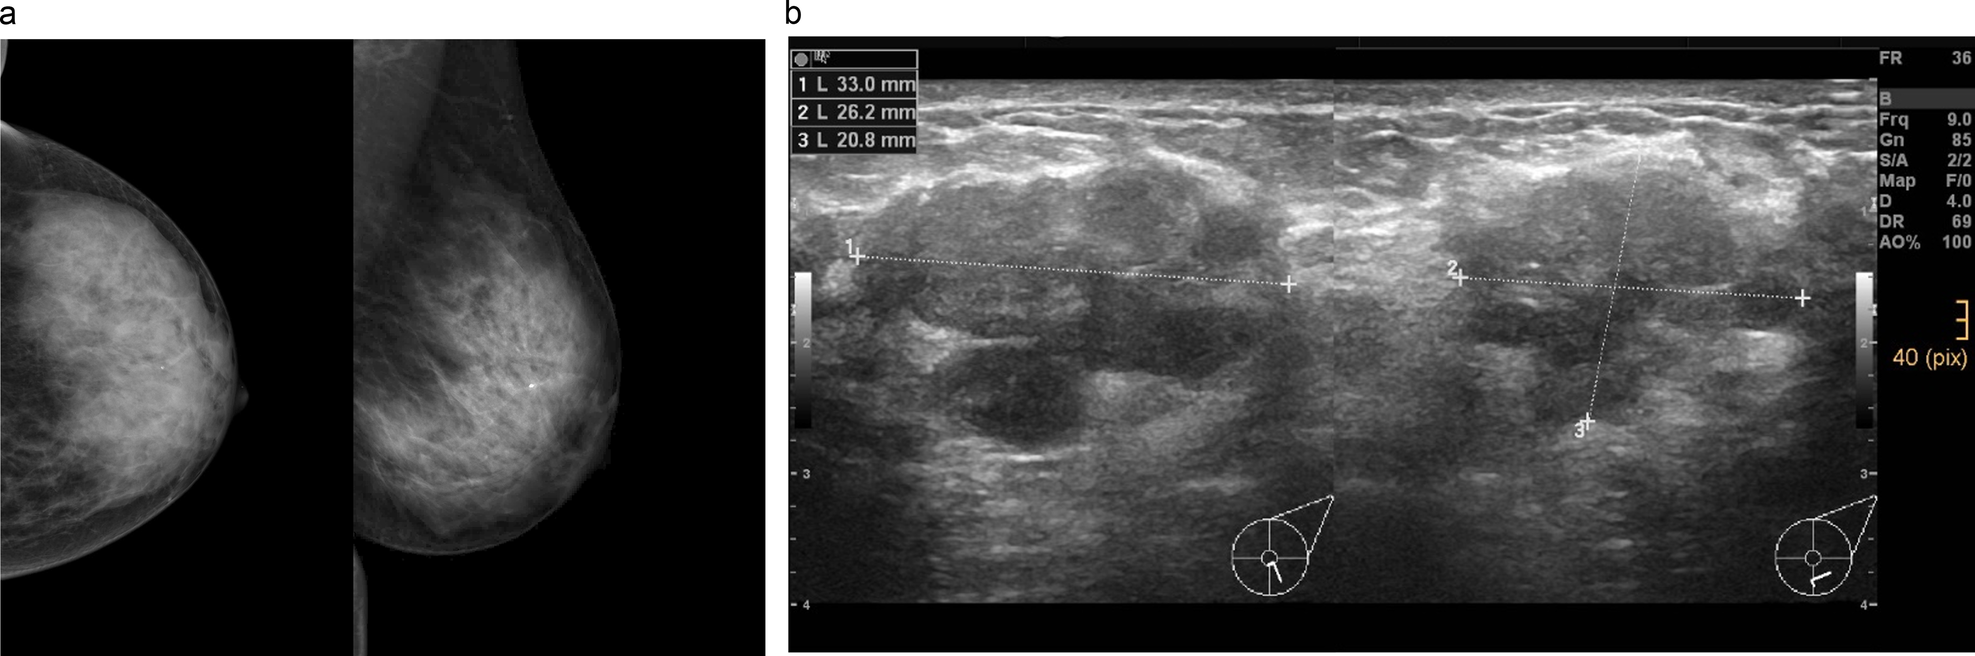

Fig. 2

45-year-old woman without significant family/personal risk factors for breast cancer undergoing first breast cancer screening examination. In the left mammogram (a cranio-caudal and mediolateral oblique projections), extremely dense breast tissue can be observed, and no suspicious findings could be identified, only a typical benign calcification can be recognized in the retromamillary region. At supplemental ultrasound (b) performed on the same day, a suspicious mass up to 3.3 cm could be identified at 6 o’clock in the left breast. Ultrasound-guided biopsy was performed, and the lesion histologically corresponded to a NST moderately differentiated invasive ductal carcinoma